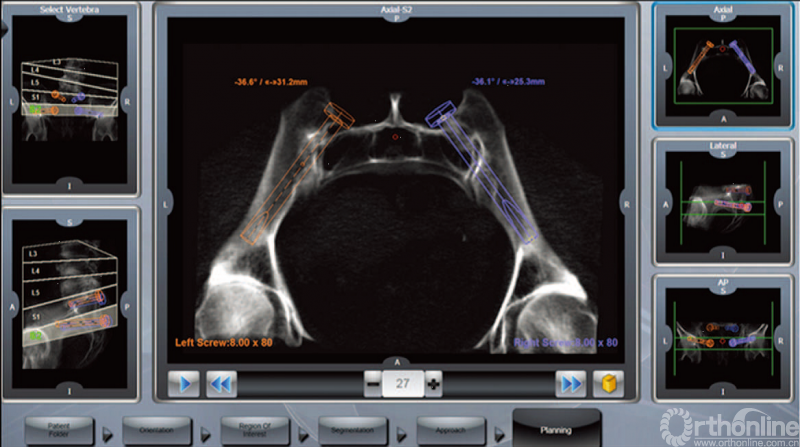

机器人辅助下行骶髂关节螺钉置入的术前计划窗口_Mazor机器人